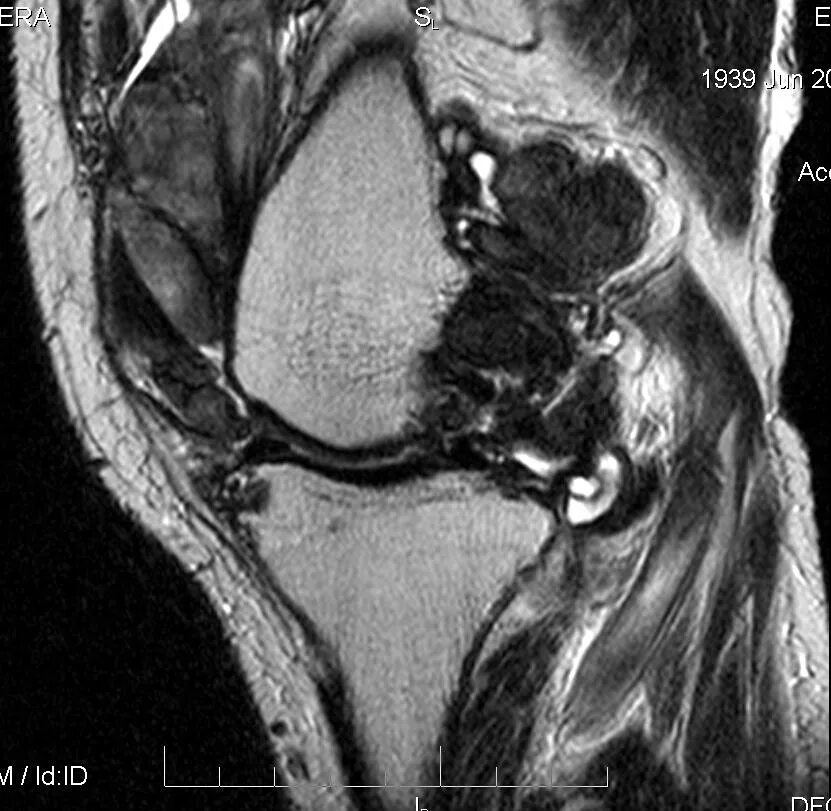

Пигментный виллонодулярный синовит